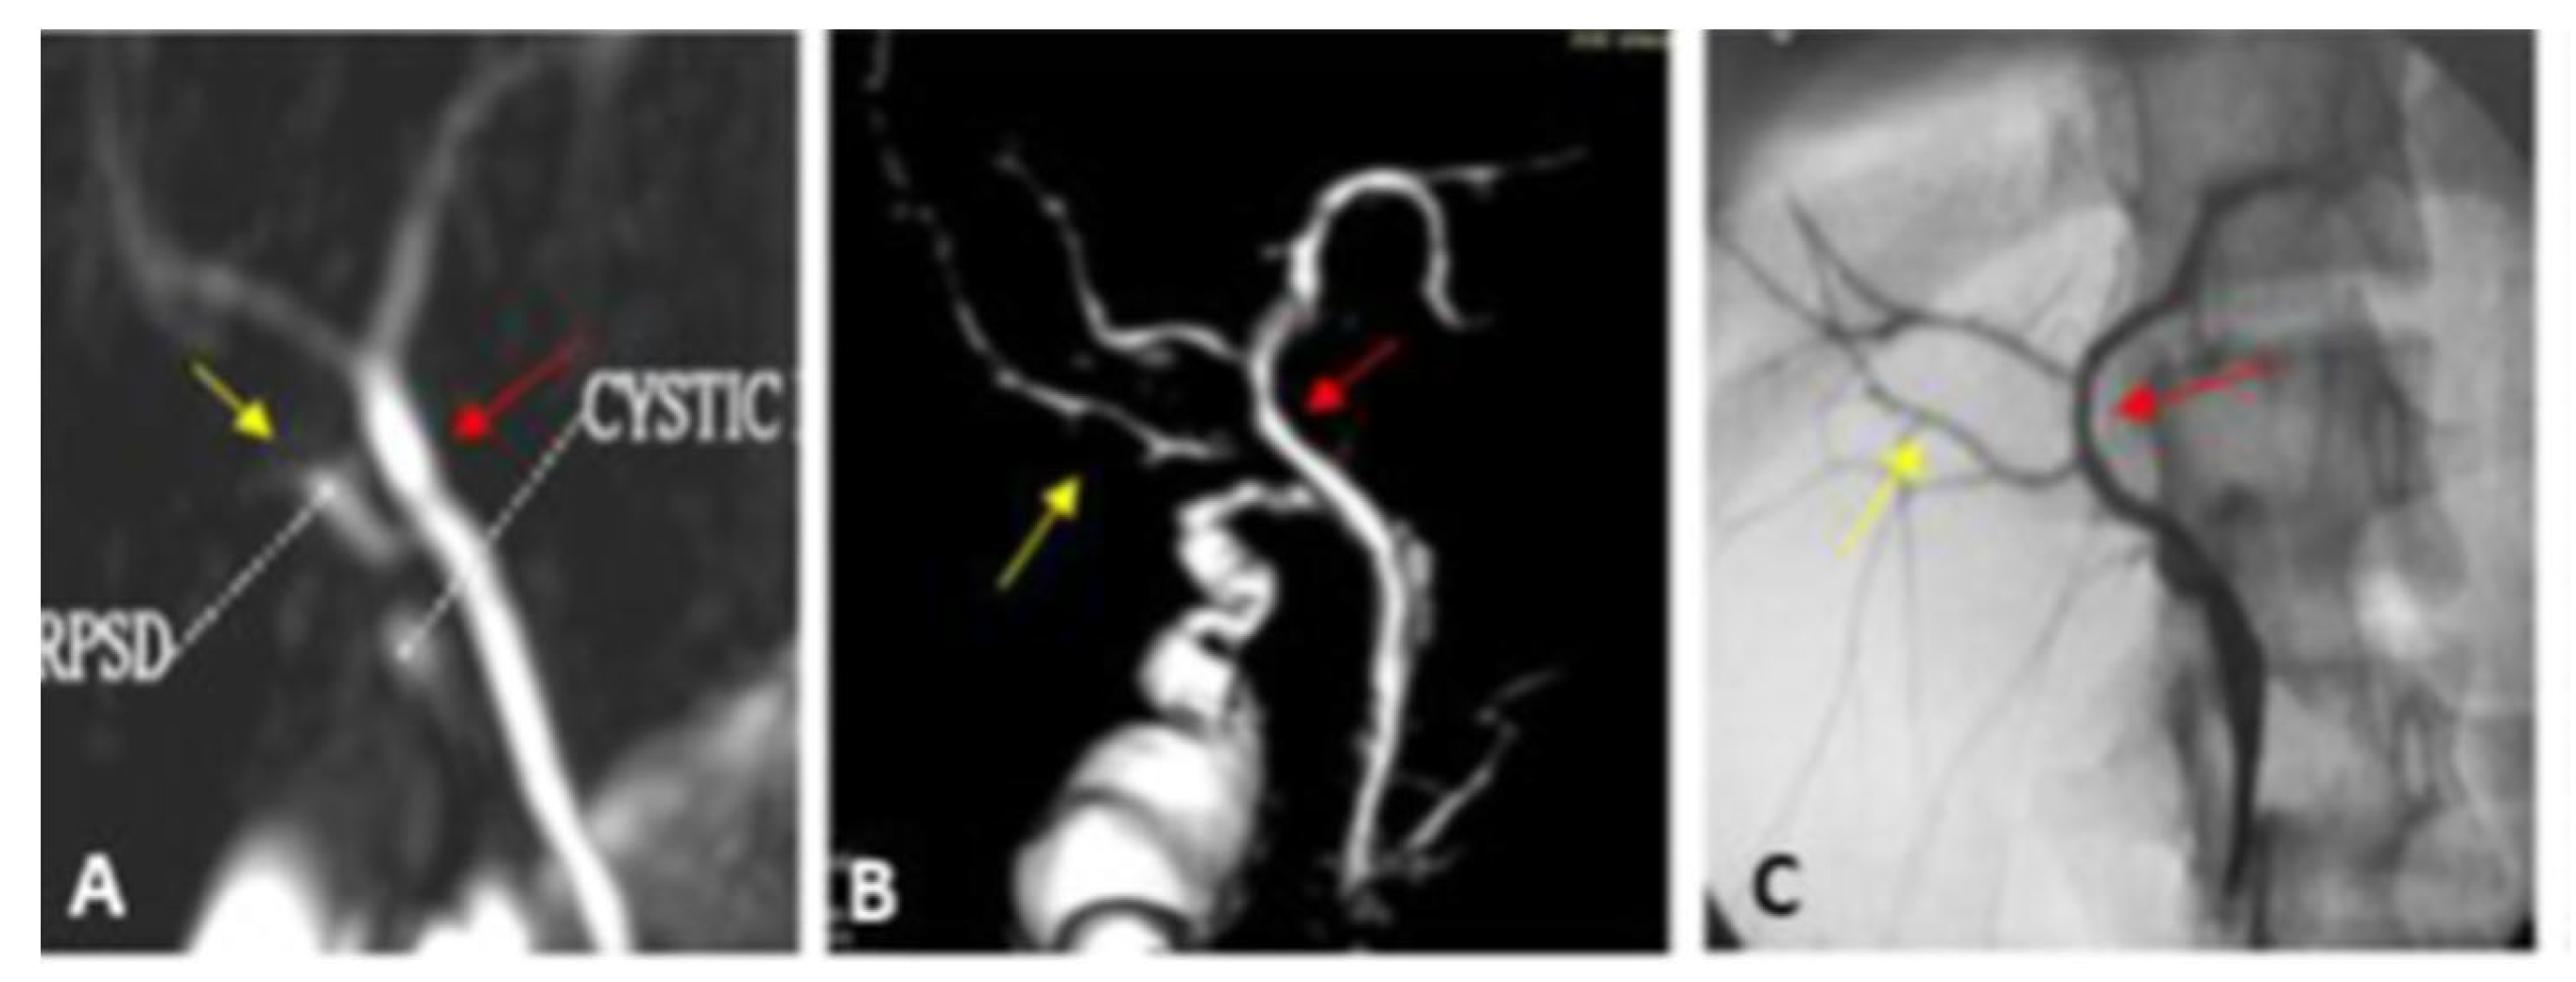

| Type I | The RPSD drains into the proximal part of the RHD (distance more than 1 cm from the hepatic confluence) | 23 (65.7) | 22 (62.9) | Very short RHD |

| Type II | Trifurcation | 4 (11.4) | 6 (17.1) | |

| Type III | Anomalous RPSD insertion | 4 (11.4) | 4 (11.4) | |

| A | Insertion of RP into the LT hepatic duct | 2 | 2 | |

| B | Insertion of RP into the CHD | 2 | 2 | |

| Type IV | Insertion of RHD in the cystic duct | 3 (8.6) | 3 (8.6) | |

| Type VII Unclassified | Trifurcation + accessory duct | 1 (2.9) | - | The acute angle between RPSD and RASD |